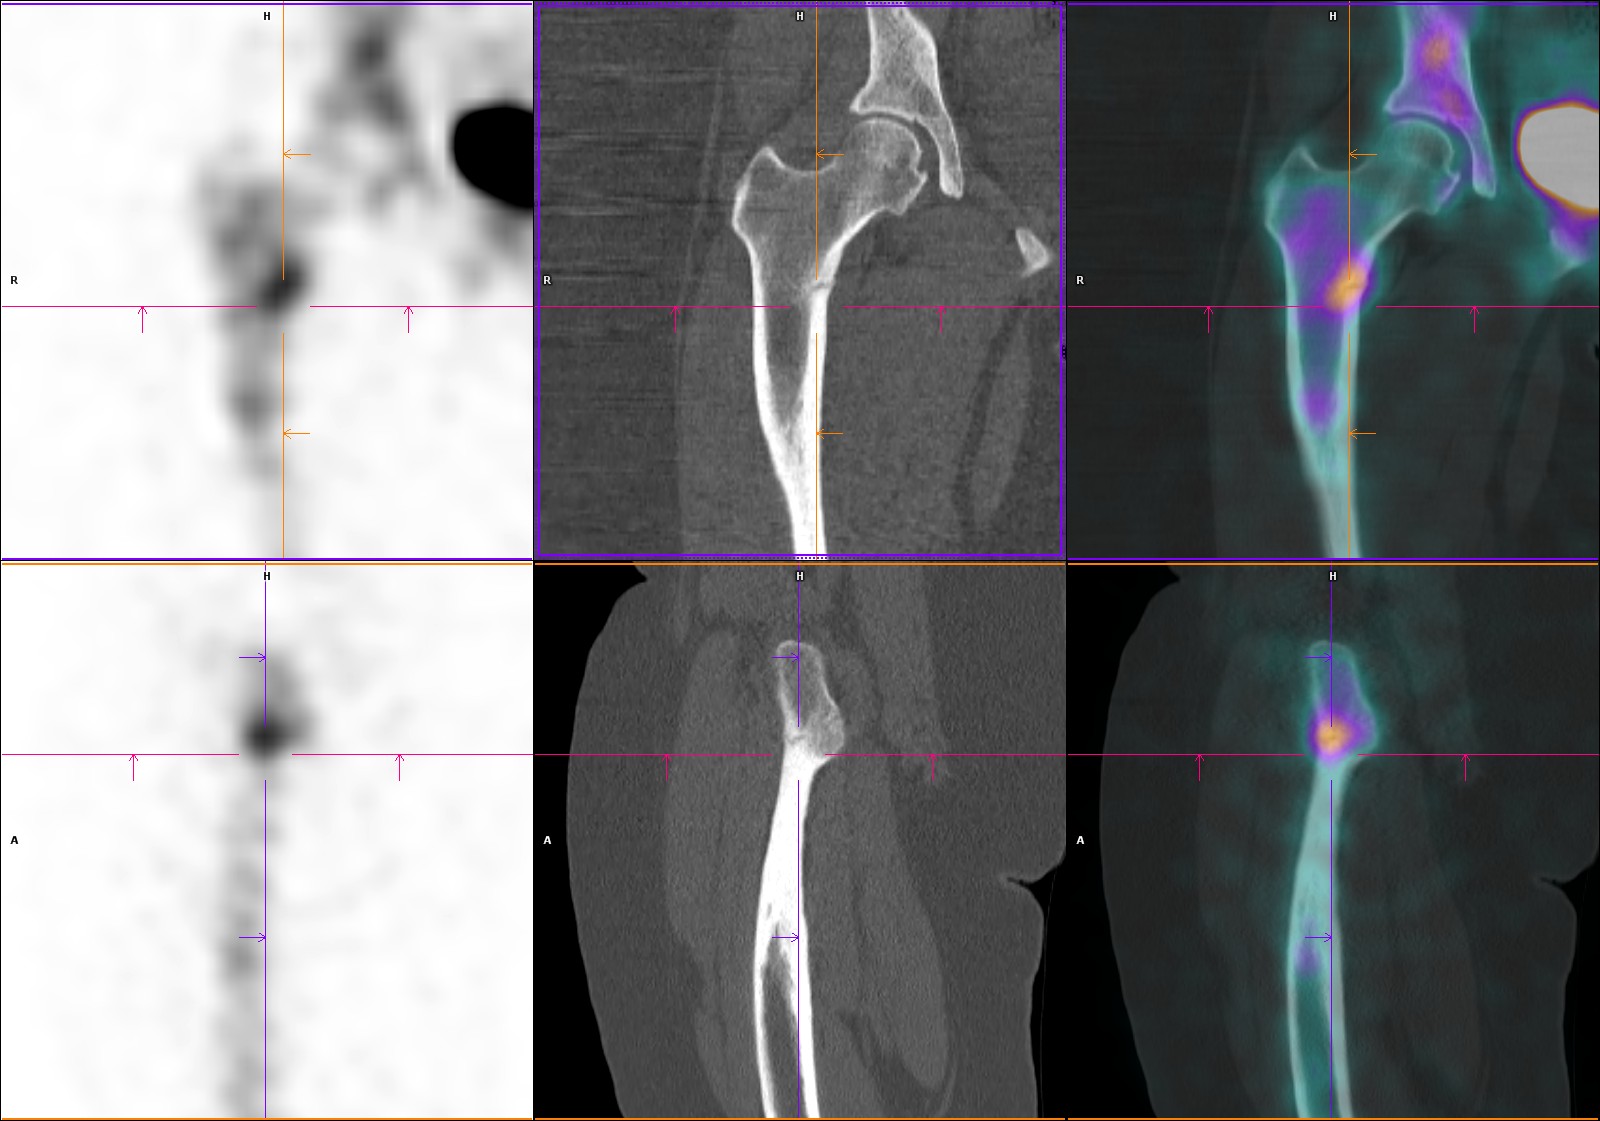

Hyperfixations en regard d’encoches corticales radiotransparentes perpendiculaires à l’axe de l’os, des métaphyses fémorales bilatérales et de la métaphyse tibiale droite (en zones portantes).

Aspect typique de stries de Looser-Milkman, spécifiques de l’ostéomalacie.

Stries de Looser-Milkman (fractures de stress chez les patients atteints d’ostéomalacie)